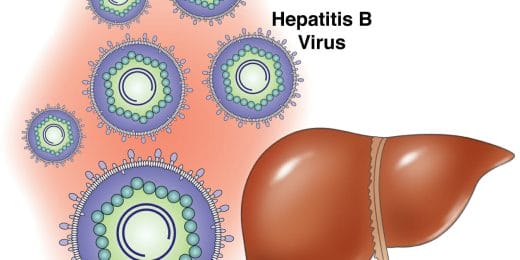

Hepatitis

Er zijn twee hoofdsoorten hepatitis (leverontsteking), ...